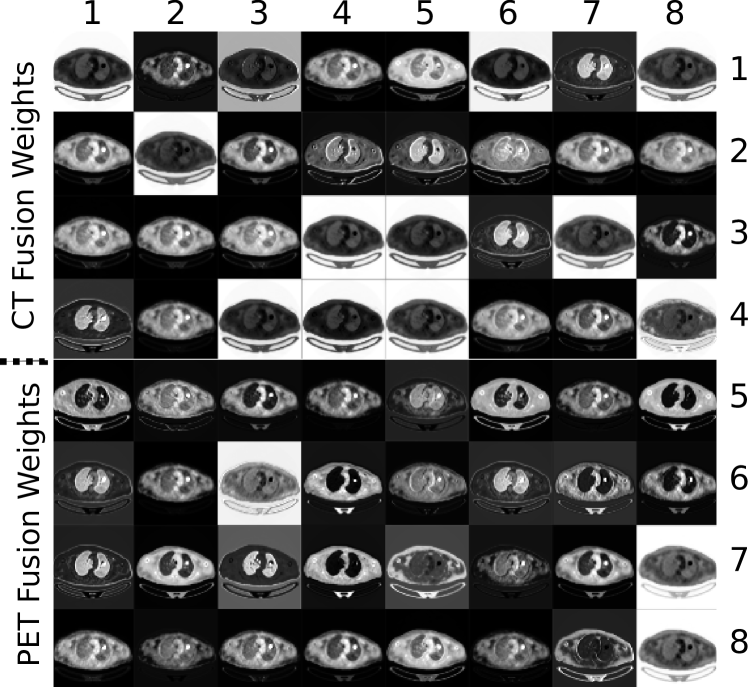

Fig. 7 depicts the co-learned fusion maps that were derived for an image with a single tumor; a larger version is included as Fig. S5 in the Supplementary Materials. In the figure, each feature map channel has been independently normalized so that their real valued pixels could be viewed in the paper. In any particular channel, a higher absolute intensity implies a greater importance placed on that pixel during fusion. The figure shows how different information is prioritized differently for each region. For example, the 7th CT fusion channel (row 1, column 7) places a greater emphasis on the lungs while the 26th PET fusion channel (row 8, column 2) places the greatest emphasis on the tumor. The figure also indicates that the fusion weights are derived from features of both modalities. For example, the 7th CT fusion channel (row 1, column 7) emphasizes the lungs including the area that contains the tumor. Meanwhile, the 13th CT fusion channel (row 2, column 5) also emphasizes the lungs but de-emphasizes the area containing the tumor. Further analyses are included in Section SIII of the Supplementary Materials.

The fusion maps shown in Fig. 7 demonstrate that our co-learning CNN can derive spatially varying fusion maps for images that contain multiple structures that have different fusion requirements. Our CNN does not need to divide the problem into distinct tasks for each ROI but rather can derive the relevant fusion information in an end-to-end manner. For example, the 7th CT fusion channel (row 1, column 7) and the 13th CT fusion channel (row 2, column 5) emphasize the lung fields relative to the area containing the tumor. We suggest the co-learning unit has produced these specific fusion channels because (in combination with other channels) they contain information to distinguish the lung fields from any tumors they may contain. It is well-established that the lung fields can be identified using CT data alone [57], and it was expected that the co-learning CNN would operate in a similar fashion. The fusion maps automatically derived by our co-learning CNN prioritize the CT data for the lung field ROIs, consistent with this expectation. Similar patterns for lung fields are noticed in the fusion maps of other PET-CT images.

While it may appear that several channels in the fusion map are redundant (similar in appearance to other channels), this is merely a visualization issue caused by normalizing 32-bit floating point greyscale images for display within the paper. As shown in Fig. S4 in the Supplementary Materials, PET fusion channels 33 to 37 (row 13, columns 1 to 5) appear visually similar but closer examination of the distribution of fusion weights within the images indicates that each channel prioritizes information in subtly different ways. Section SIII in the Supplementary Materials contains a detailed example showing the differences in these visually similar fusion channels and their impact in the analysis of heterogeneous tumors, which is an important clinical application. We suggest that the capacity of our co-learning CNN to derive these subtly different fusion weights enables more precise integration of the complementary information in each modality when compared with uniform fusion (see Fig. 8).